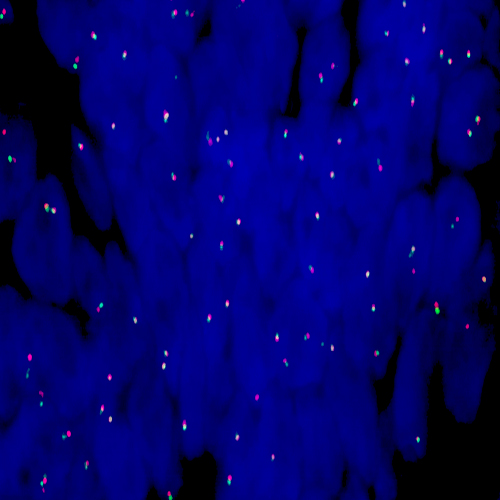

Human thymoma: immunohistochemical staining for CD1a. Note the neoplastic cells show a moderate to strong and distinct membrane staining reaction. CD1a: clone MTB1

CD1a is a protein of 43 to 49 kD expressed on dendritic cells and cortical thymocytes. CD1a antigen expression has been shown to be useful in differentiating Langerhans cells, powerful antigen presenting cells present in skin and epithelia, from interdigitating cells. Immunohistochemical studies for CD1a antigen have reported a reduction in epidermal Langerhans cells in graft versus host disease and the participation of CD1a antigen-positive dendritic cells in atherosclerotic lesion formation and asthmatic inflammation.

Clone MTB1 detects cortical thymocytes, Langerhans cells in epidermis, interdigitating cells of dermis and interdigitating cells of stratified squamous epithelium of tonsil. Clone MTB1 may also detect small focal groups of lymphocytes outside the germinal centers of tonsil indicating a cross-reaction with CD1b antigen.